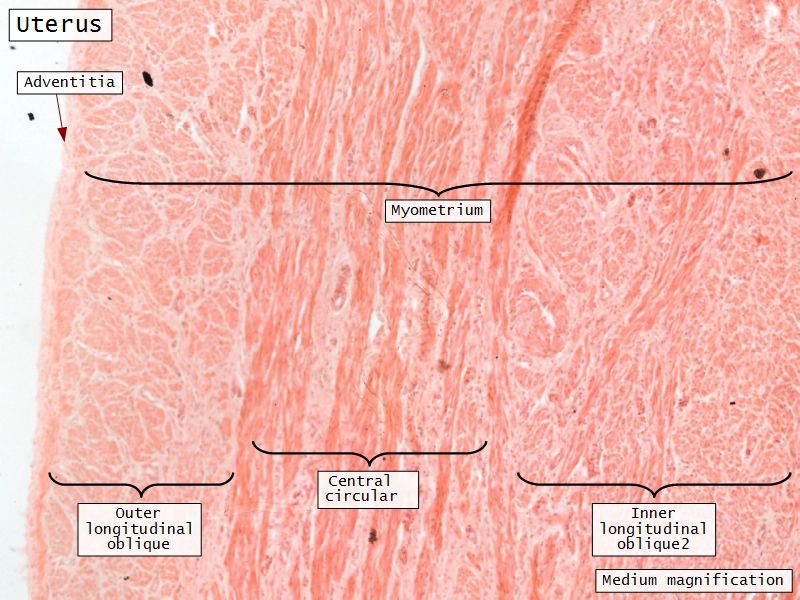

Myometrium

- 3 layers indistinct smooth

- Inner longitudinal/oblique

- Central circular

- Large blood vessels

- Stratum vasculare

- Outer longitudinal/oblique

Adventitia

- Or serosa

- Covers myometrium